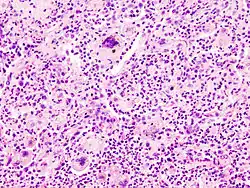

Foreign-body giant cells form when a subject is exposed to a foreign substance. Exogenous substances can include talc or sutures. As with other types of giant cells, epithelioid macrophages fusing together causes these giant cells to form and grow.[13] In this form of giant cell, the nuclei are arranged in an overlapping manner. This giant cell is often found in tissue because of medical devices, prostheses, and biomaterials.